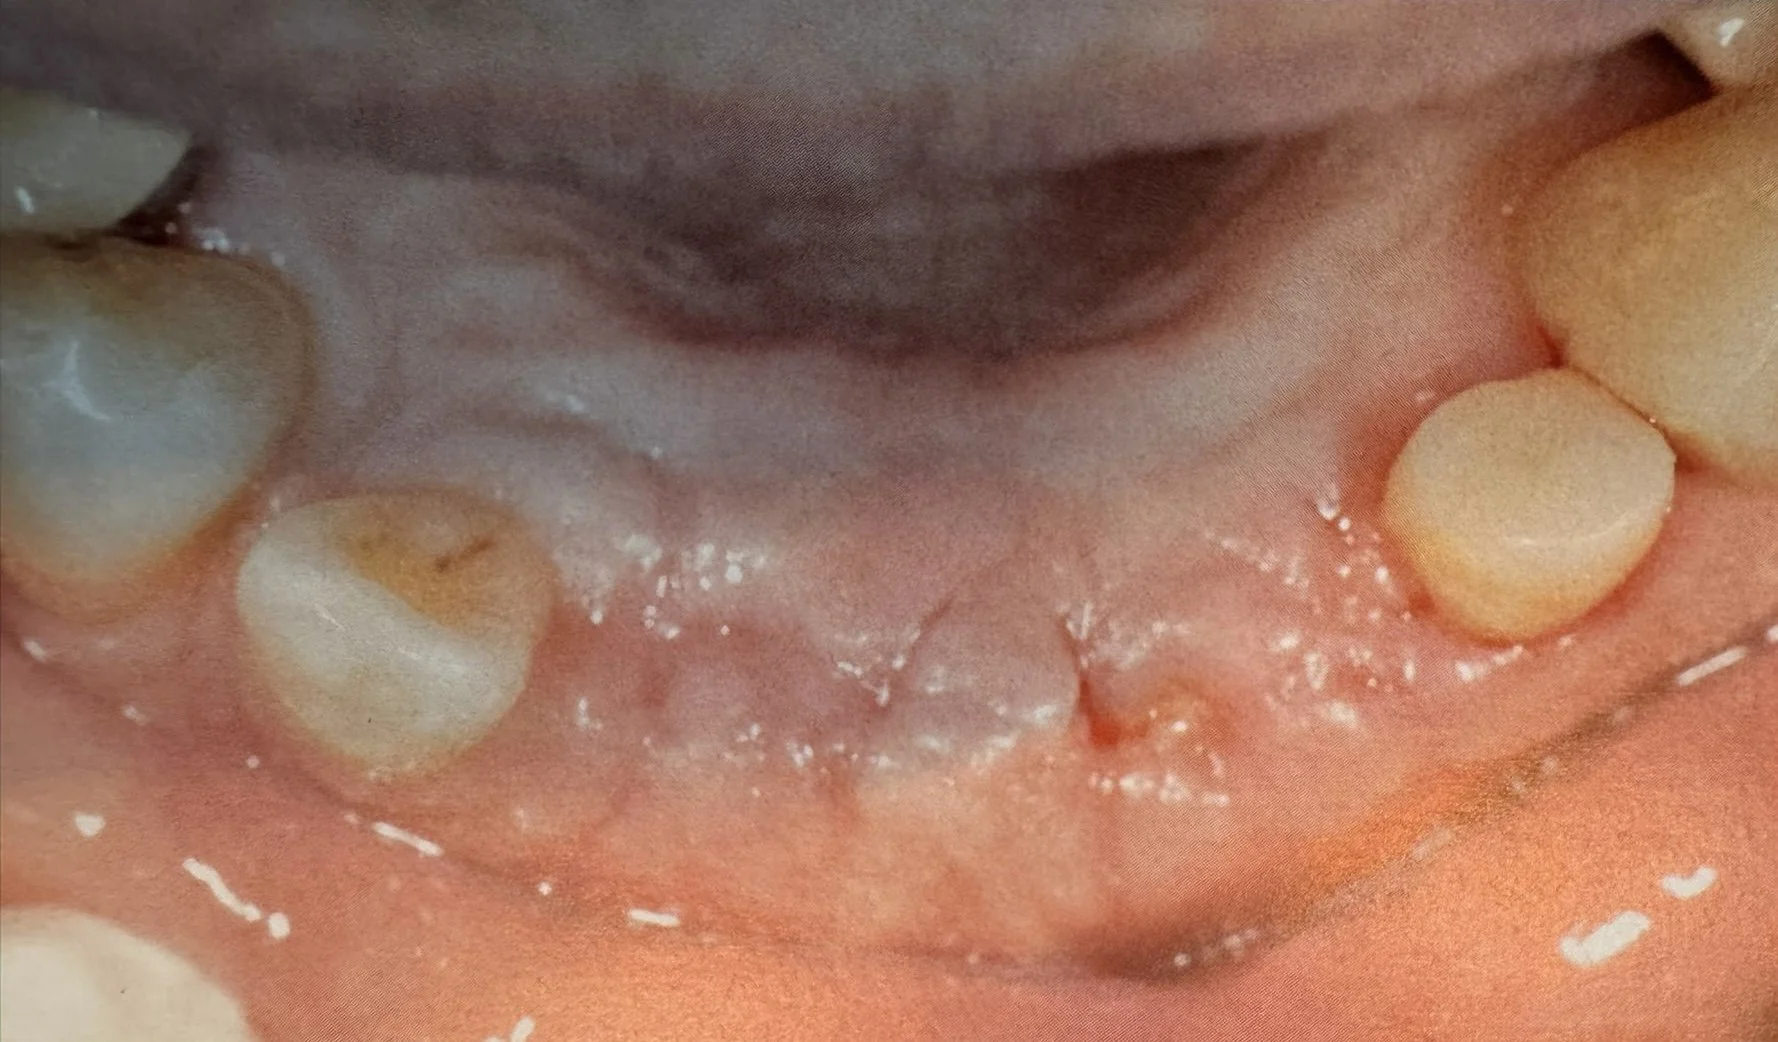

Estrazione, Rigenerazione Ossea e Riabilitazione Implantare

Riabilitazione post estrazione con impianto